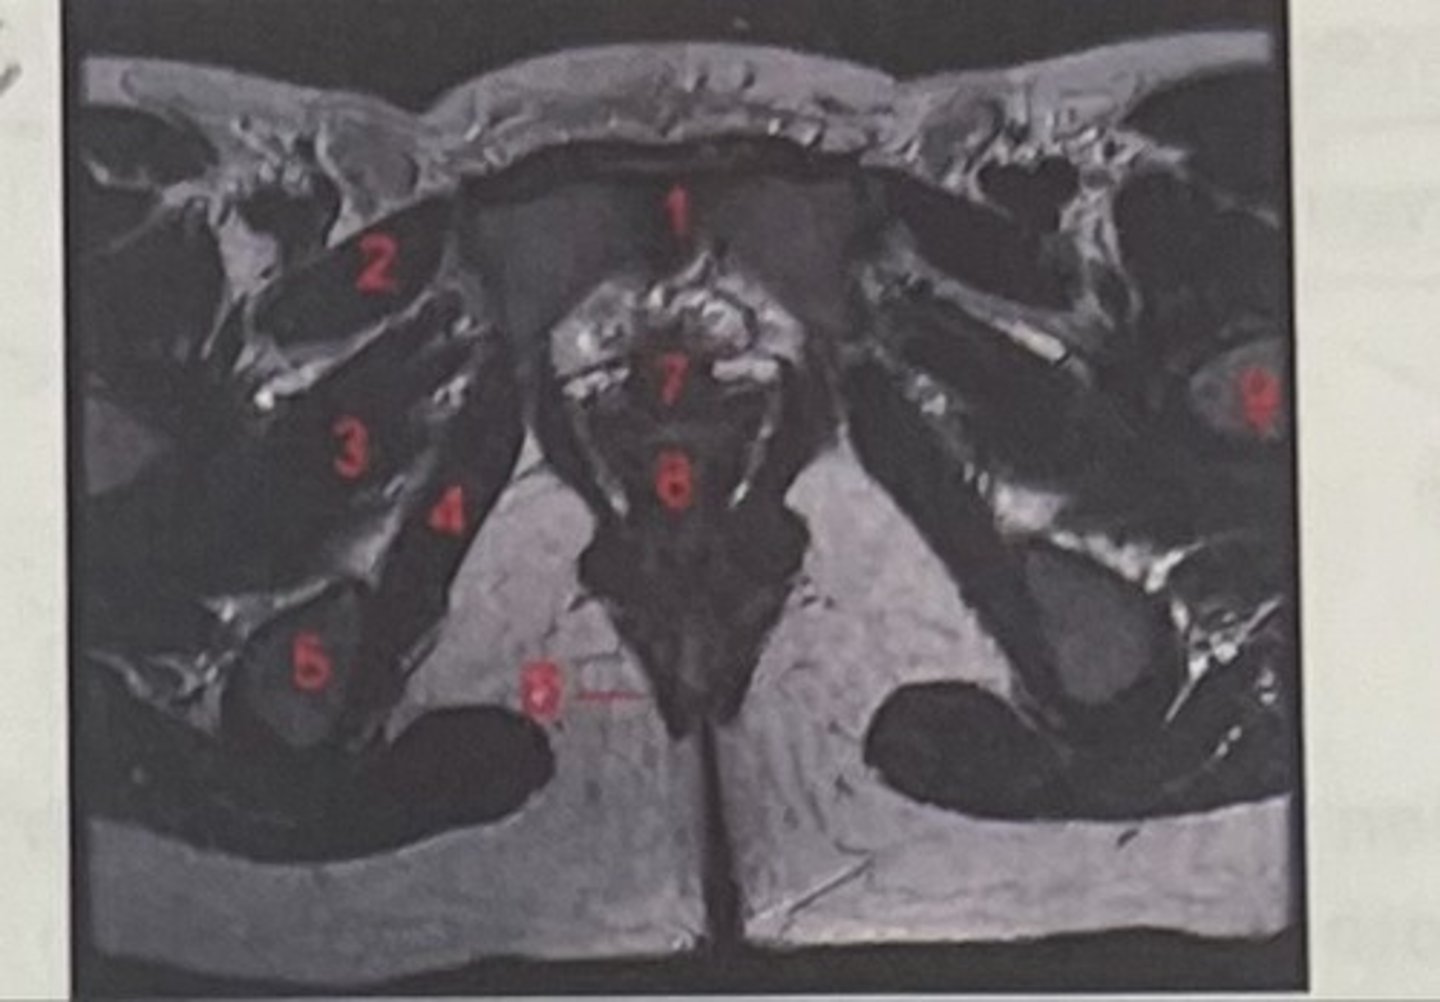

pubic symphysis

What is 1

Pectineus

What is 2

Obturator externus

What is 3

obturator internus

What is 4

ischial tuberosity

What is 5

external spincter

What is 6

Urethra

What is 7

Vagina

What is 8

Femoral nerve

What is 9

Left lung